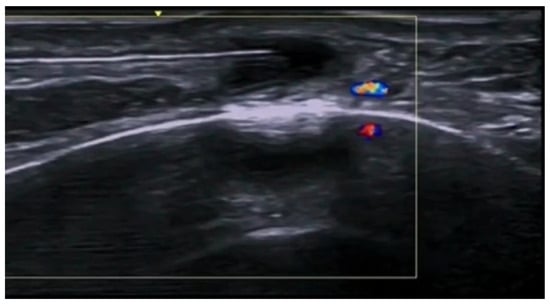

5. Specific Cutaneous Structure and Sites of Skin Disorders